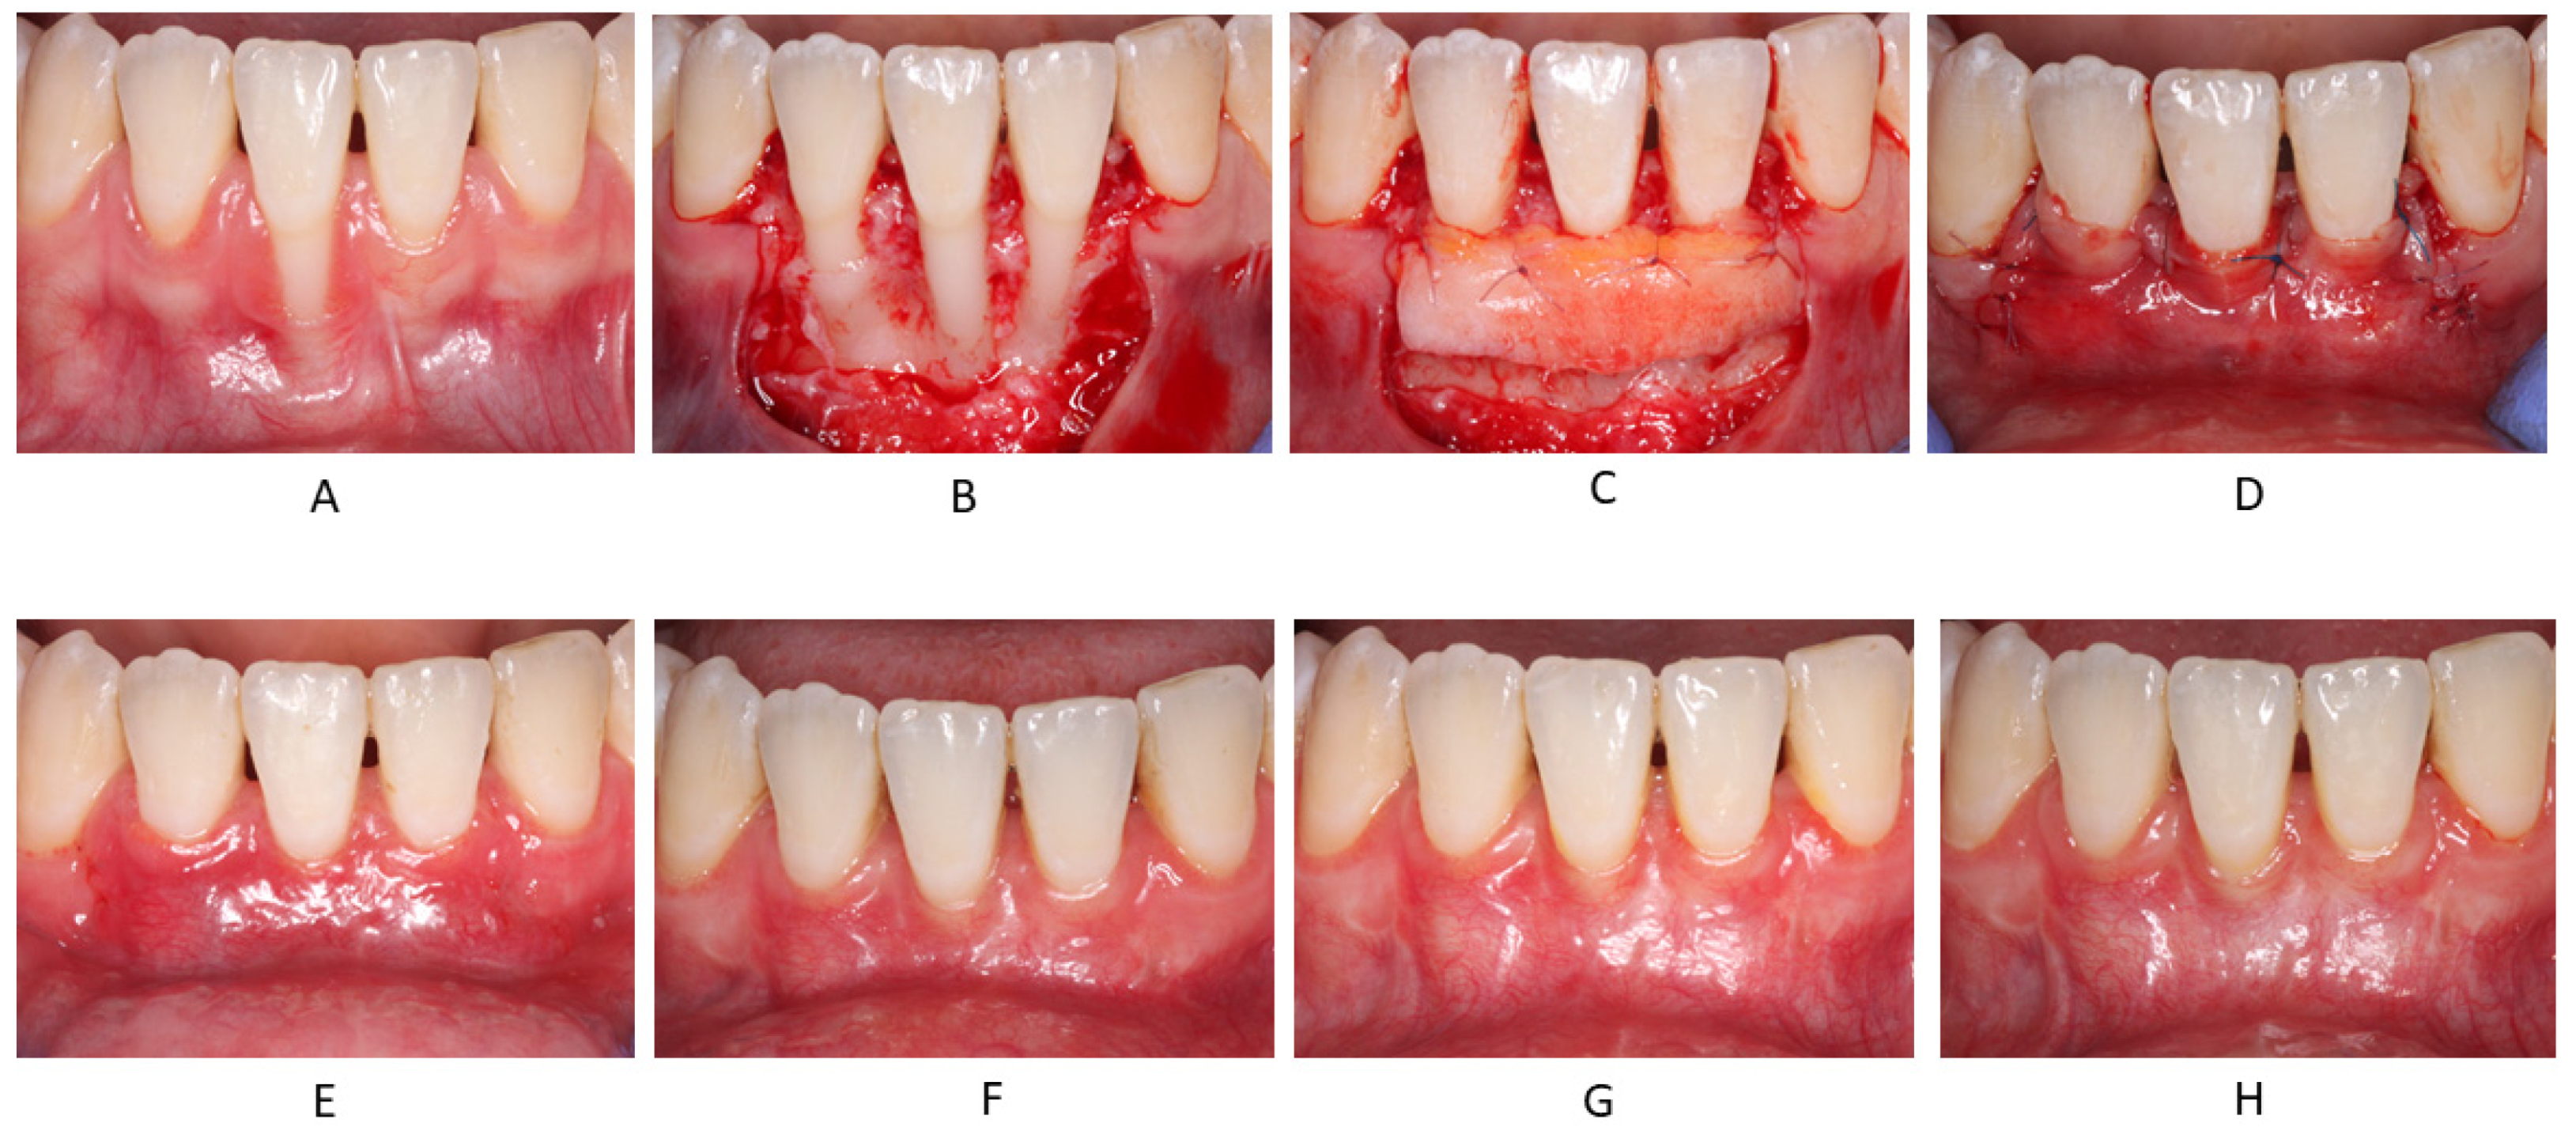

The surgical technique for gingival recession coverage was the trapezoidal-type of CAF [22], fully covering a CTG obtained by means of de-epithelialization of a free gingival graft (FGG) [23] (Figure 1).

Figure 1.

Representative case: (A) Pre-op; (B) Flap elevation; (C) Fixation of CTG at CEJ level; (D) Closure of CAF above the CEJ; (E) 2 weeks follow-up; (F) 1 month follow-up; (G) 3 months follow-up; (H) 12 months follow-up.

Postoperative healing was uneventful in all treated cases and at all follow-up visits (Figure 1). Furthermore, patients reported no events of acute post-operative pain.